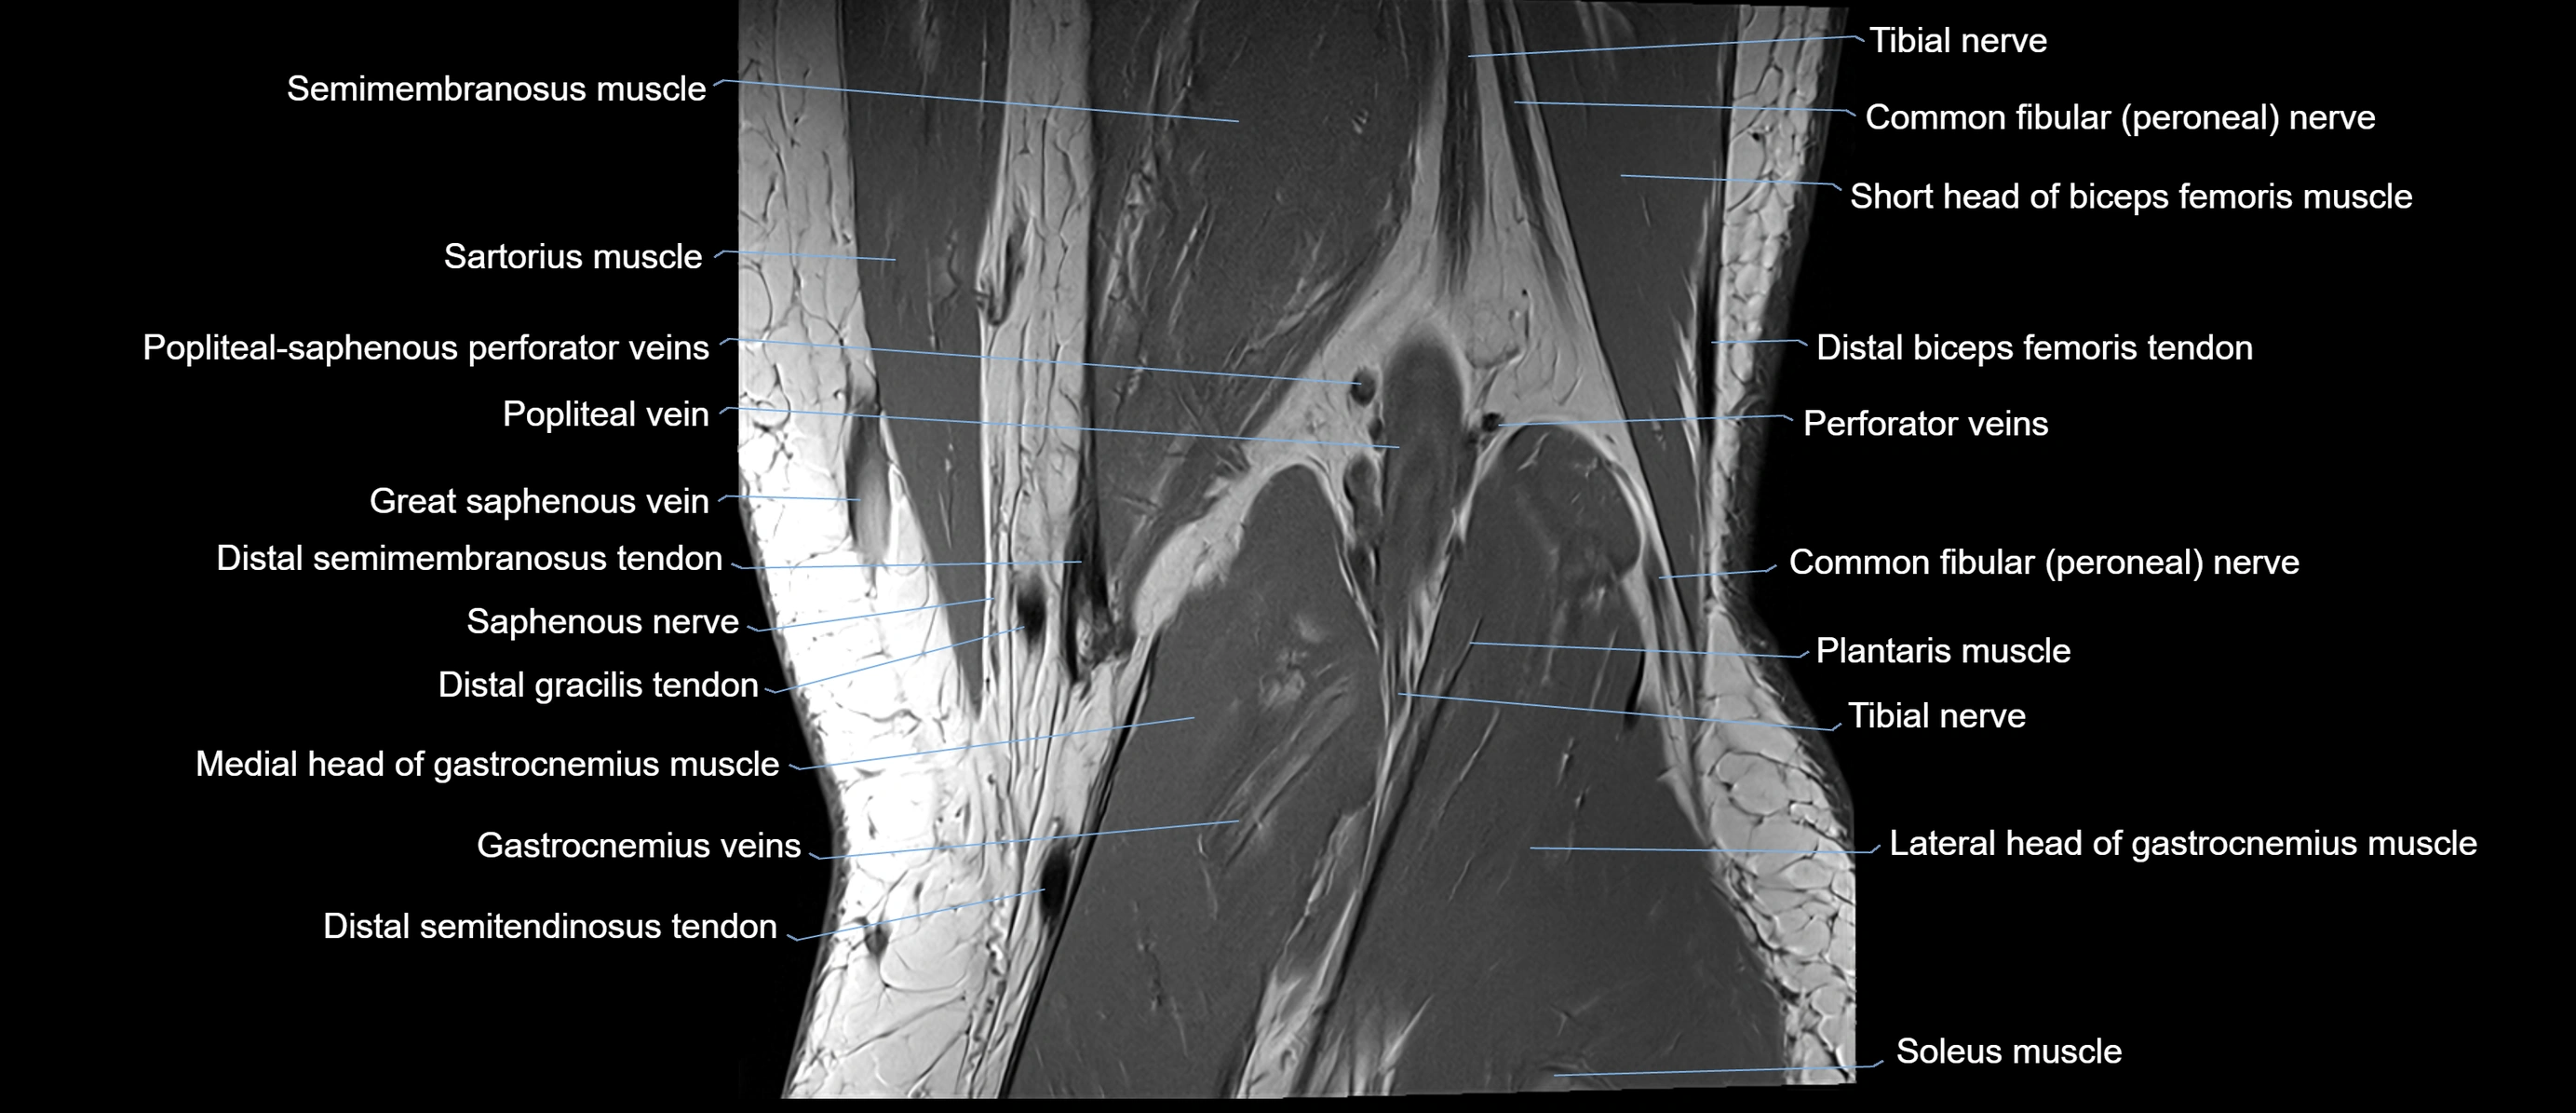

- Common fibular nerve

- Distal semitendinosus tendon

- Gracilis tendon (Distal)

- Medial gastrocnemius tendon

- Medial head of gastrocnemius muscle

- Medial sural cutaneous nerve

- Popliteal artery

- Popliteal vein

- Popliteal–Saphenous perforating veins

- Saphenous nerve

- Sartorius muscle

- Semimembranosus muscle

- Semitendinosus muscle

- Soleus muscle

- Tibial nerve